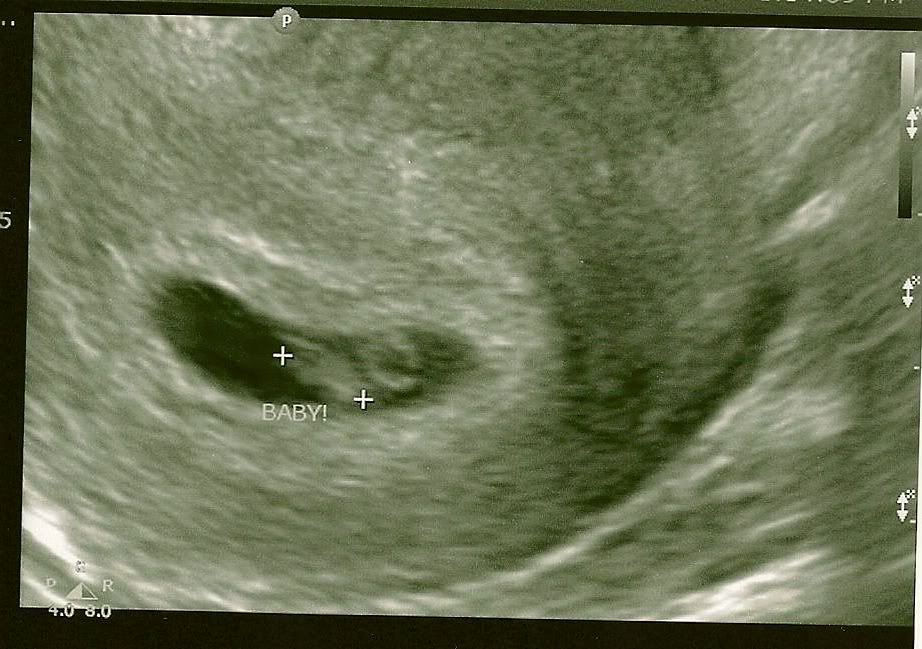

Today was our first appointment. I'm confirmed 6 1/2 weeks due June 10th. We got an unexpected u/s and baby looks perfect. The heartbeat was 120 fetal pole and yolk sac are right on track. ![]()